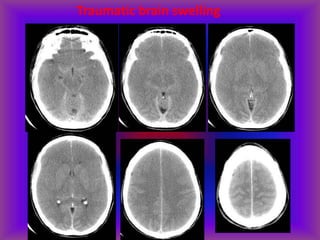

Traumatic Brain Swelling

Know your basal cisterns!

Effacement of basal cisterns

Traumatic brain swelling with

downward herniation